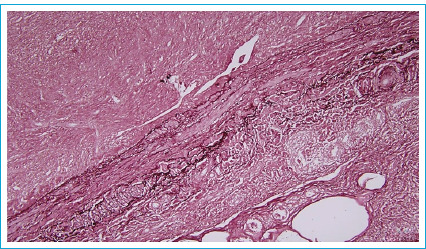

腹股沟肿块有多种原因,从腹股沟疝到软组织肉瘤。一个不太常见的原因是血管起源。与动脉动脉瘤不同,静脉动脉瘤很少出现,治疗经验也很少。一名32岁男性患者因左侧腹股沟肿块扩大,初步诊断为腹股沟疝而转介到我们诊所。多普勒超声显示一直径8厘米的动脉瘤性大隐静脉段位于腹股沟韧带下方。未完全切除扩张节段。大隐静脉动脉瘤的外科修复需要切除扩张节段,并根据静脉瓣膜衰竭进行完整的静脉切除。如果检测到大隐静脉动脉瘤,由于其衰弱性和可能破裂,应首先选择手术入路。

Inguinal masses have a large variety of causes, ranging from inguinal hernias to soft tissue sarcomas. One of the less prevalent causes is vascular origin. Venous aneurysms, unlike their arterial counterparts, are seen seldomly and experience in management of these cases is scarce. A 32-year-old male patient was referred to our clinic due to an enlarging left inguinal mass with a preliminary diagnosis of inguinal hernia. Doppler ultrasonography revealed an eight cm in diameter aneurysmatic Great Saphenous Vein segment located just below the inguinal ligament. Dilated segment was excised without complete resection. Removal of the dilated segment and performing complete venous resection depending on venous valvular failure constitutes surgical repair of Great Saphenous Vein aneurysms. Surgical approach should be primarily selected if Great Saphenous Vein aneurysm is detected due to its debilitating nature and possible rupture.